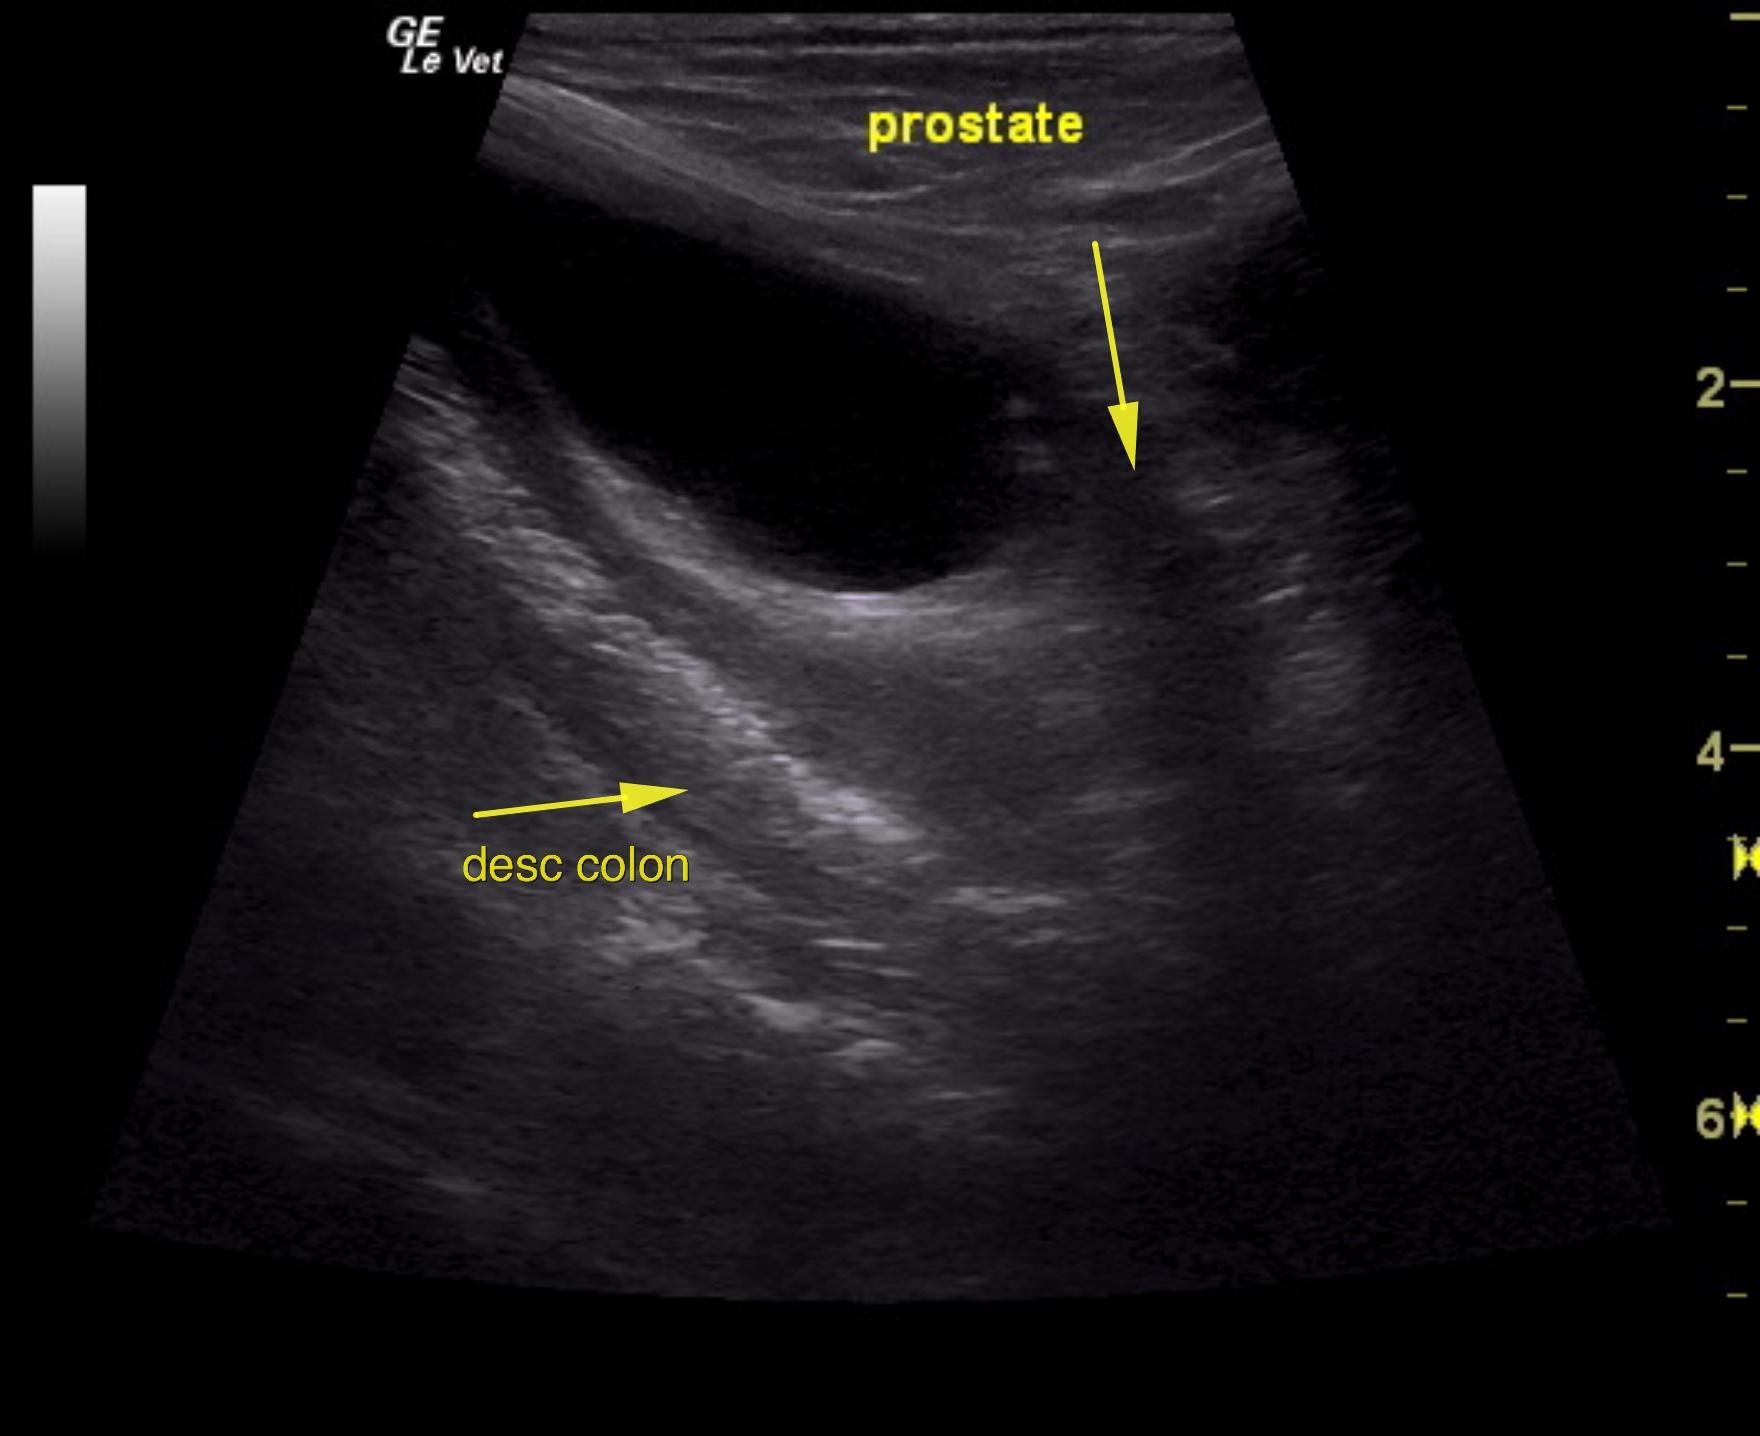

The urinary bladder itself presented minor thickening and minor debris. A tubular structure was noted in a position between the colon and the urinary bladder with dilation.

An 11-year-old NM Poodle was presented for evaluation of back pain and dark urine. Urinalysis and blood work were both unremarkable.

Purulent material was obtained on ultrasound-guided centesis without complications. However, reactive mesentery was noted throughout the pelvis. The position of this tube would fit with a uterus. This patient may be a hermaphrodite with secondary pyometra. I cannot make a direct connection from the tubular structure to the prostate itself as they appear to be separate. I recommend exploratory surgery with removal of this structure. The ureters do not appear to be involved. The position and structure would be that of a uterus. Therefore, treatment for pancreatitis and localized infection in the region of the pelvis would be recommended with IV fluid support, broad spectrum antibiotics such as Enrofloxacin and Clindamycin combination as well as exploratory surgery. If the tubular structure is confirmed to be a uterus and hermaphroditism then examination for possible ovaries would also be warranted even though none were visible in the image set. Regardless, this tubular structure necessitates surgical resection.